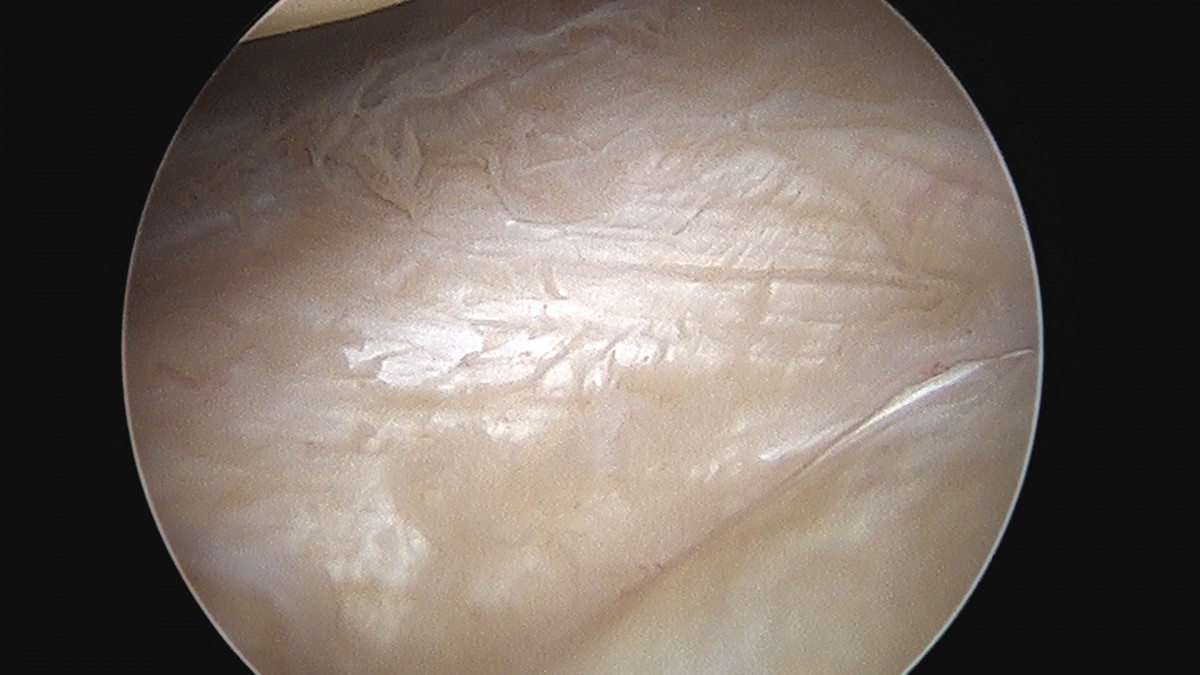

이재상원장님 어깨 이두박건 절제술 정하O 환자

dae765e4d9ac96aee867c9d6292d8784_1758006930_1385.jpg